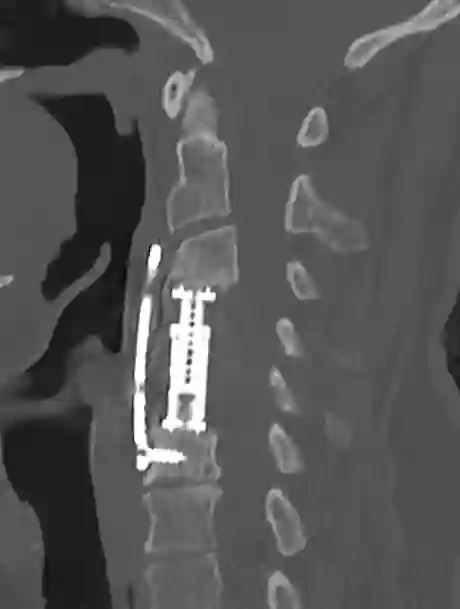

Korporektomie CT

CT einer Halswirbelsäule nach durchgeführter Korporektomie von HWK4 und HWK5 mit einem Cage und Platte.